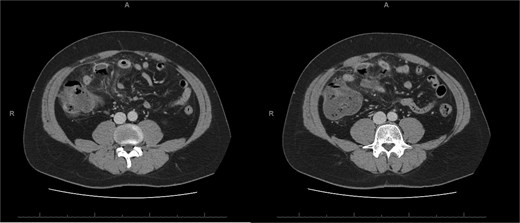

A 76-year-old female with a 3-day history of left upper abdominal pain, vomiting, and haematochezia. Her history included pulmonary embolism, multiple deep vein thromboses, with no ongoing anticoagulation, and an open partial colectomy for complicated diverticulitis a decade earlier. On admission, she was afebrile but tachycardic and showed localized tenderness in the left hypochondrium. Laboratory revealed leucocytosis with a white blood cell count (WBC) of 12 G/L, elevated C-reactive protein (CRP) of 46 mg/L, and hyperlactatemia of 2.6 mmol/l. Enhanced computed tomography (E-CT) revealed jejunal venous ischemia in the left upper quadrant, secondary to extensive porto-mesenteric thrombosis with reduced bowel wall enhancement, distention, and free intraperitoneal fluid (Fig. 1). She was managed conservatively with unfractionated heparin (UFH) with a bolus of 5000 U/l followed by 30 000 U/l/24 h (target INR 0.35–0.7), Piperacillin-Tazobactam, and bowel rest. After 48 h of monitoring in the intensive care unit (ICU), she exhibited marked biological and clinical improvement. E-CT on the third day showed restored bowel wall enhancement and stable porto-mesenteric thrombosis (Fig. 2). She was discharged on therapeutic low molecular weight heparin (LMWH) with enoxaparin sodium 120 mg every 12 h. At the 3-month follow-up, E-CT revealed near-complete thrombus resolution, without intestinal sequelae (Fig. 3).

Three-month E-CT of the first patient showing nearly complete thrombosis resolution, with no signs of intestinal distress.